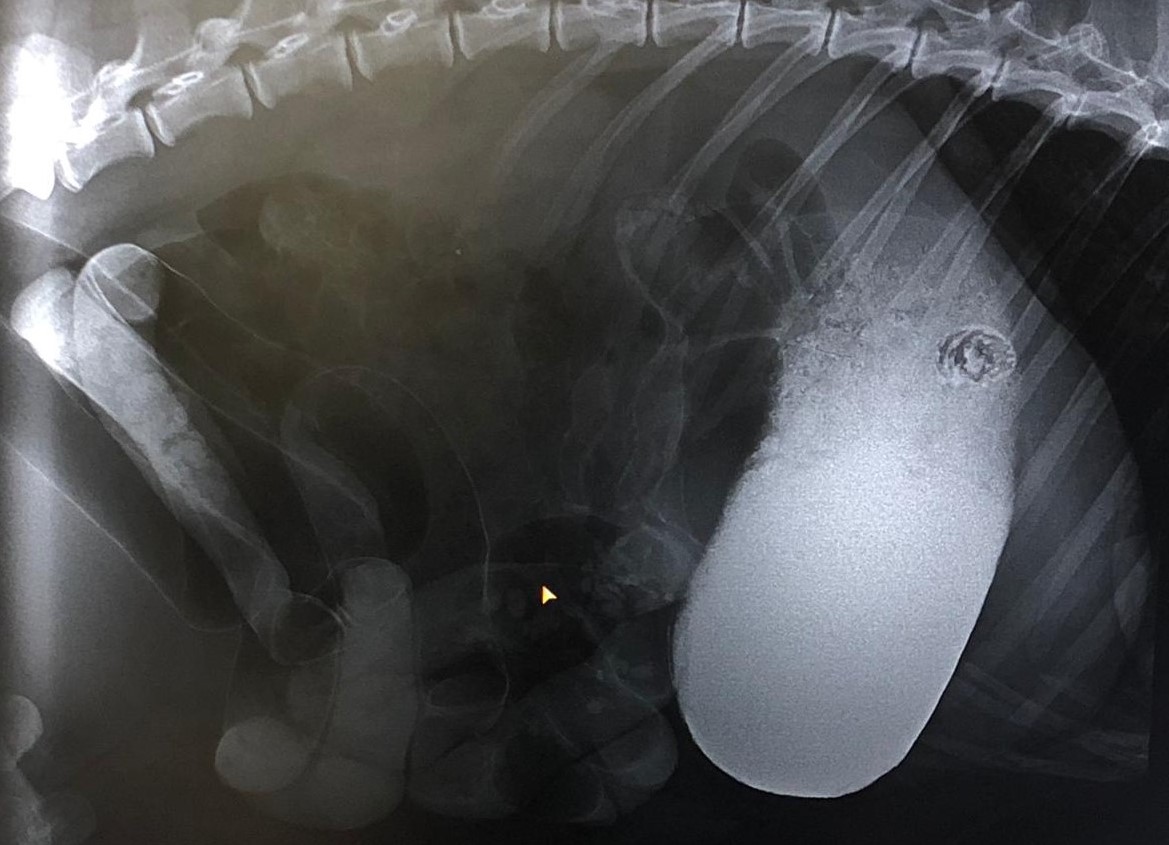

Der seltene Fall… Der verschluckte Pfirsichstein

Bei einem Minischwein konnte ein Pfirsichstein, der sich im Dünndarm direkt am Magenausgang festgesetzt hatte, entdeckt und erfolgreich durch eine Operation entfernt werden. Deshalb bitte aufpassen, gerade junge Tiere sind verspielt und verschlucken gern das Eine oder Andere….